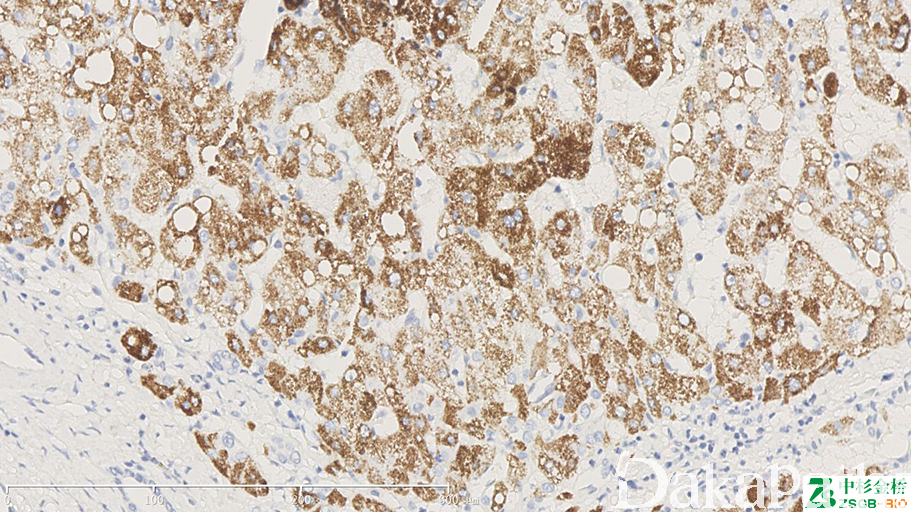

Hep-Par1

标记正常肝细胞、多数肝癌细胞。HCC 诊断中,HepPar1 是一种具有较高敏感性和特异性的标记物,它的特异性靶点在肝细胞的线粒体,可生产弥漫的颗粒状物质,胞质呈颗粒状。

信号定位: 胞质

肝细胞癌与胆管癌及转移癌的鉴别诊断;